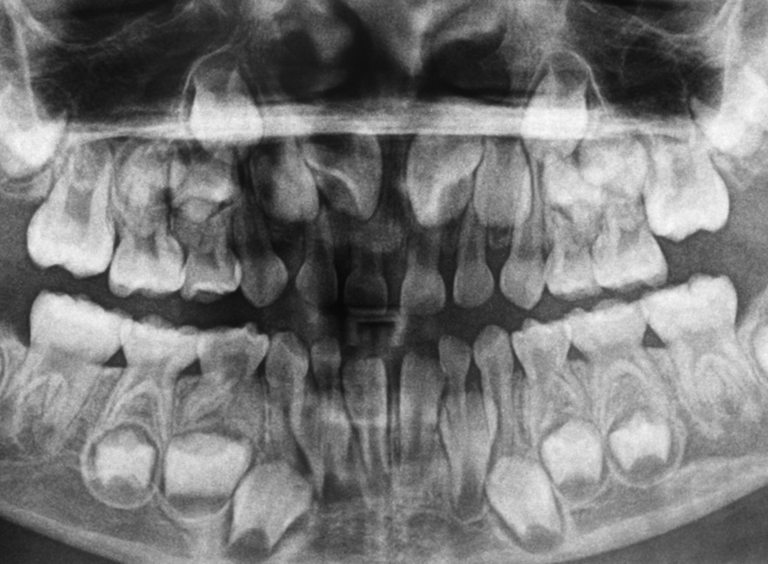

Детето разполага с 20 млечни зъба - 10 от горната страна и 10 изпод, под които са ситуирани зачатъците на бъдещите непрекъснати зъби. Първи се демонстрират долните предни резци, а последни - кътниците. Редът на рухването им е същият.

Може би сте се питали за какво просто през цялото време не ни поникват непрекъснати зъби, а би трябвало да ги сменяме. Това е по този начин, тъй като размерът на челюстта на детето е прекомерно дребен за огромните непрекъснати зъби. А в случай че оставаха с размера на млечните, при възрастния субект те щяха да бъдат малцина и с огромни дистанции между тях.